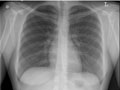

Una radiografía de pecho es una imagen del pecho que muestra el corazón, los pulmones, las vías respiratorias, los vasos sanguíneos y los ganglios linfáticos. Una radiografía de pecho también muestra los huesos de la columna vertebral y del pecho, incluidos el esternón, las costillas, la clavícula y la parte superior de la columna vertebral. Una radiografía de pecho es el examen de diagnóstico por imágenes o radiografía más común que se utiliza para detectar problemas en el pecho.

Una radiografía de pecho es una imagen del pecho que muestra el corazón, los pulmones, las vías respiratorias, los vasos sanguíneos y los ganglios linfáticos. Una radiografía de pecho también muestra los huesos de la columna vertebral y del pecho, incluidos el esternón, las costillas, la clavícula y la parte superior de la columna vertebral.

Los pulmones tienen un aspecto normal en cuanto al tamaño y a la forma, y el tejido de los pulmones tiene un aspecto normal. No pueden observarse crecimientos ni otras masas dentro de los pulmones. Los espacios pleurales (los espacios que rodean los pulmones) también tienen un aspecto normal. Vea una radiografía de pecho normal.

El corazón tiene un aspecto normal en cuanto al tamaño y a la forma, y el tejido cardíaco tiene un aspecto normal. Los vasos sanguíneos que van al corazón y que salen de este también son normales en cuanto al tamaño, a la forma y a la apariencia.

Los huesos, incluidas la columna vertebral y las costillas, tienen un aspecto normal.

El diafragma tiene un aspecto normal en cuanto a la forma y a la ubicación.

No se observa una acumulación anormal de líquido o aire; tampoco se observan objetos extraños.